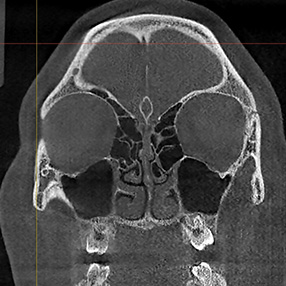

※ 축농증 수술 후 생길 수 있는 부작용으로는 출혈, 감염, 염증이 있을 수 있습니다.

본 사진은 의료기관에서 진료를 본 환자이고, 전후 사진 인물이 동일인이며,동일조건에서 촬영이 되었습니다.